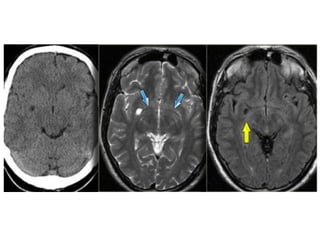

Lacunar infarcts

• Lacunar infarcts are small infarcts in the deeper parts of

the brain (basal ganglia, thalamus, white matter) and in

the brain stem.

• Lacunar infarcts are caused by occlusion of a single

deep penetrating artery.

• Lacunar infarcts account for 25% of all ischemic strokes.

• Atherosclerosis is the most common cause of lacunar

infarcts followed by emboli.

NECT

• Because of their small size, most "true" lacunar

infarcts not seen on CT scans

• Visible lacunes seen as small, well

circumscribed areas of low (CSF) attenuation

• Usually seen in setting of more extensive white

matter disease; typically multiple

MR Findings

• Tl WI: Small, well circumscribed hypointense foci

• T2WI: Small, well circumscribed hyperintense foci

• FLAIR:Typically increased in signal

• DWI

o Restricted diffusion (hyperintense) if acute/subacute

o May show small lesions otherwise undetectable

• Tl C+: May enhance if late acute/early subacute

• MRA: Normal

Lacunes may be confused with other empty

spaces, such as enlarged perivascular

Virchow-Robin spaces (VRS).

The VRS are extensions of the

subarachnoid space that accompany

vessels entering the brain parenchyma.